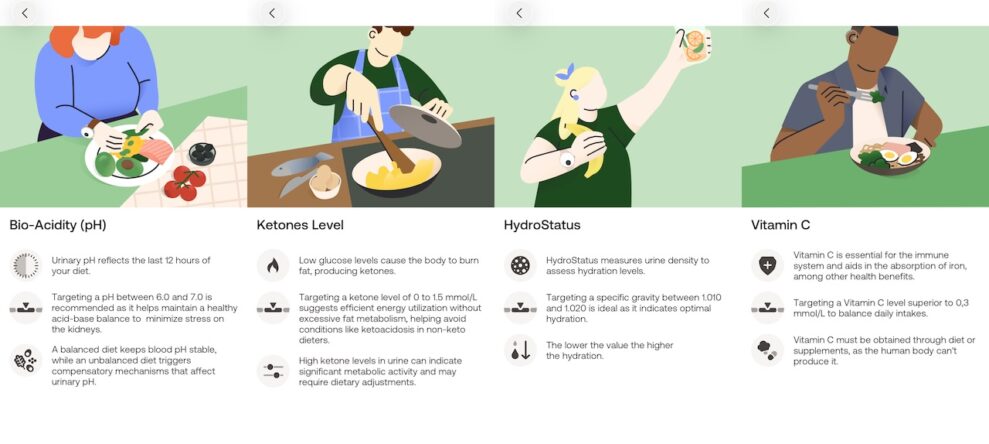

En bra stund efter att man lämnat provet plingar det till i appen och så får man sina resultat. I mitt fall låg PH-värdet inom det normala, om än på gränsen till lågt. Ett lågt värde innebär att man bör se över sin livsstil och vanor. Mina C-vitaminnivåer var optimala så vitamintabletten på morgonen gör tydligen nytta, då jag inte äter mycket citrusfrukter. Ketonmätningen visar normalt, så mitt intag och förbränning av kolhydrater är balanserat. Ett högt värde kunde varit tecken på diabetes, eller för all del en keto-kost. Däremot tyckte appen att jag var lite uttorkad och tyckte att jag borde dricka mer vatten.